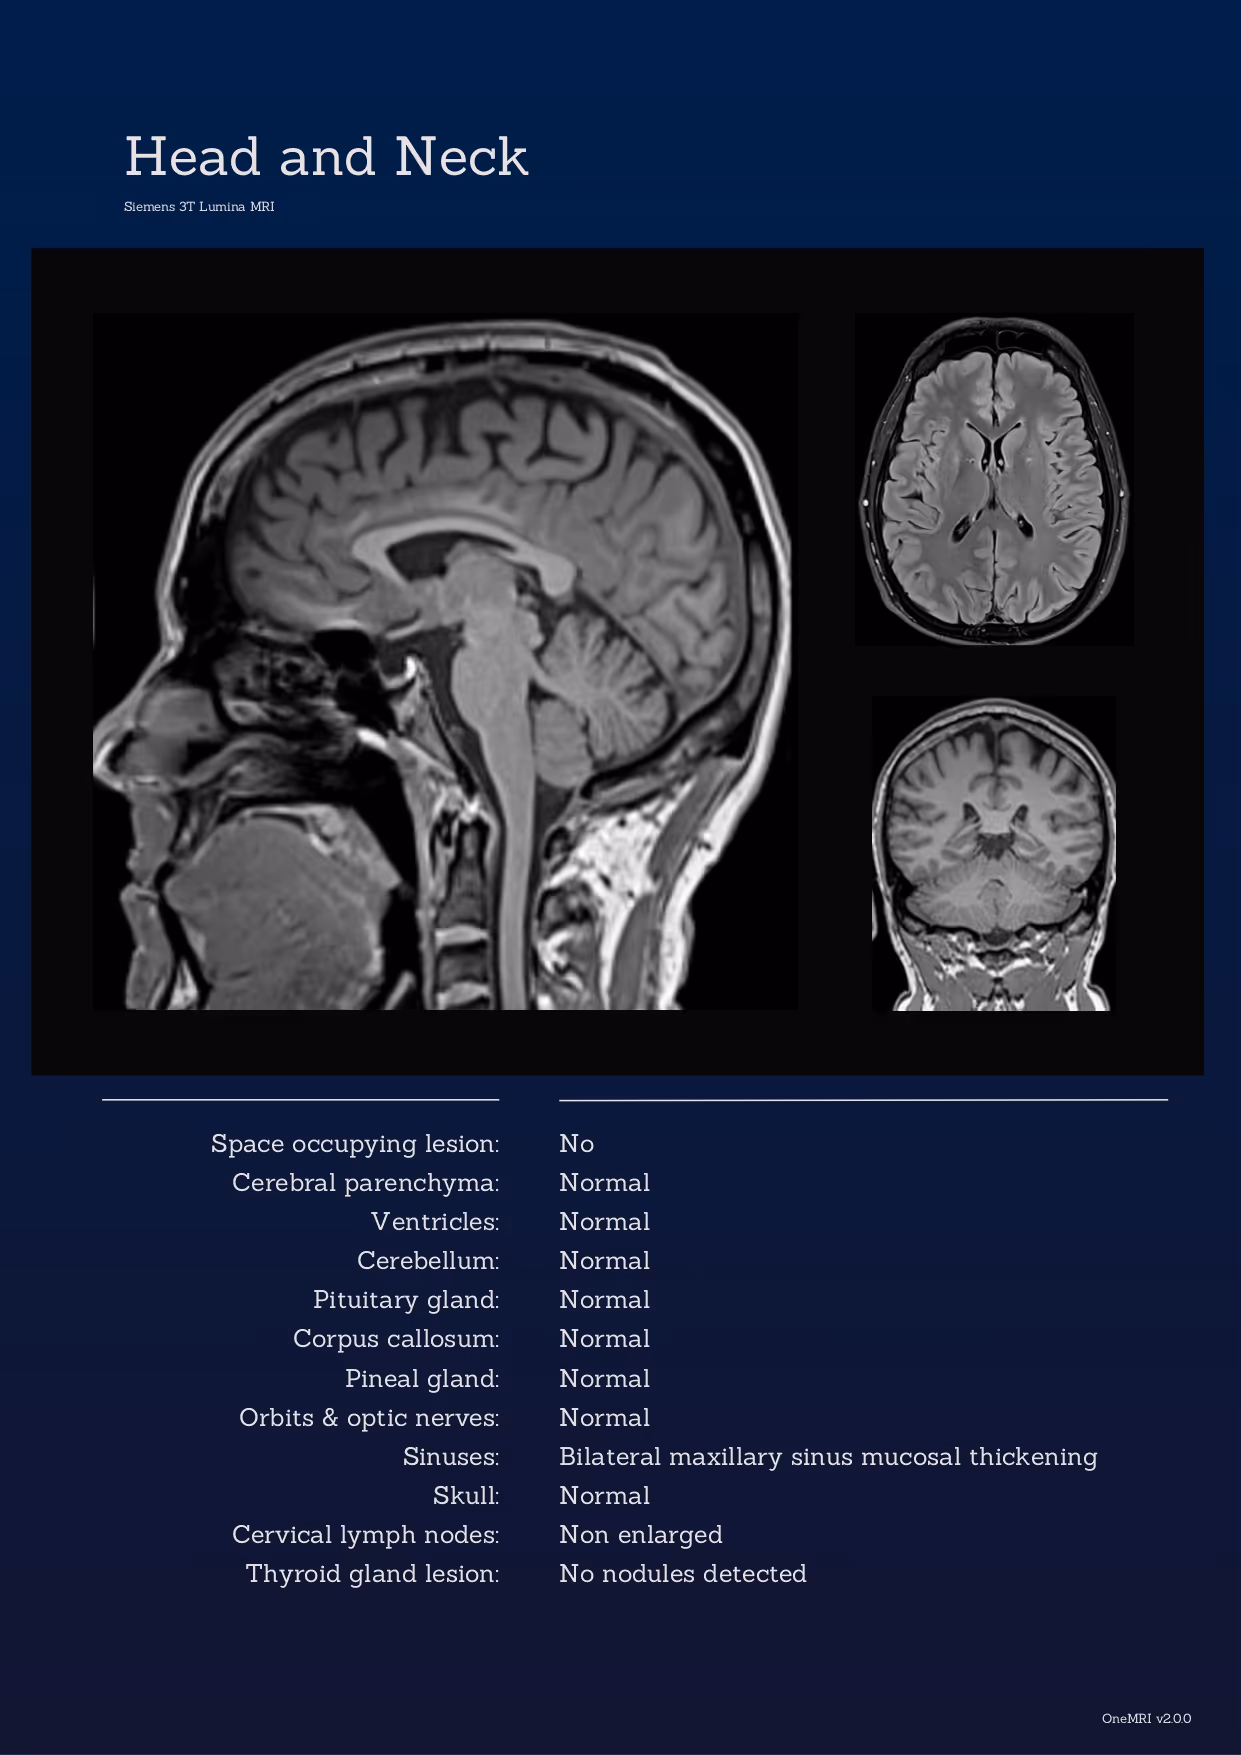

Your report is more than a summary. It is a complete, visual overview of your health. Each scan includes annotated images, clear explanations of any findings, and a summary that highlights areas for follow-up.

Tap images below to explore examples.